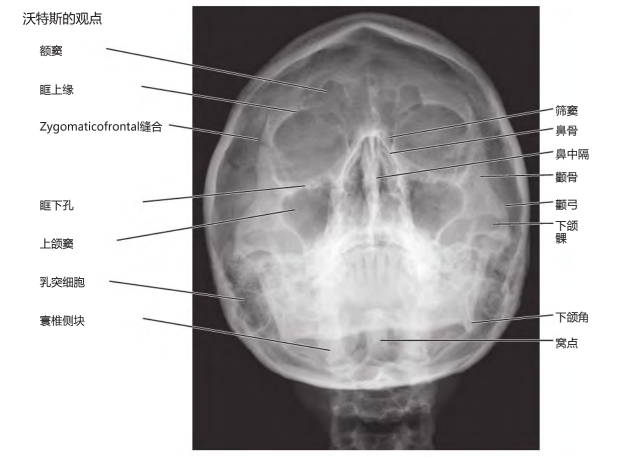

部分电子书预览